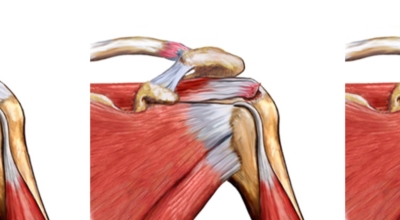

회전근개파열이란?

회전근개 증후군은 회전근개에 변형과 파열이 생긴 질환을 말해요. 회전근개란 어깨와 팔을 연결하는 4개의 근육(극상근, 극하근, 소원근, 겹갑하근) 및 힘줄로 이루어져 있는 것으로 보입니다. 어깨 근육통을 막연히 오십견으로 알고 방치하다가 치료 시기가 늦어지는 경우가 있답니다. 적절한 시기에 병원에 가는 것이 필요해요.